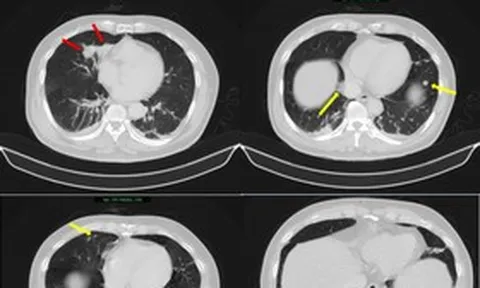

Phát hiện "thứ đáng sợ" gần 12kg trong tử cung của cô gái 25 tuổi

Cô gái trẻ có bụng to bất thường như mang thai đôi, kèm huyết khối tĩnh mạch đùi trái gần tắc hoàn toàn, tiềm ẩn nguy cơ cao thuyên tắc phổi và biến cố tim mạch khi phẫu thuật, đe dọa tính mạng.